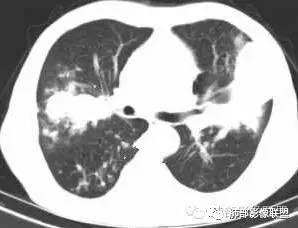

病例三:男,74岁,双肺上叶不规则软组织肿块,内侧与肺门相连,形成“支气管树爬行征”。

![]() |